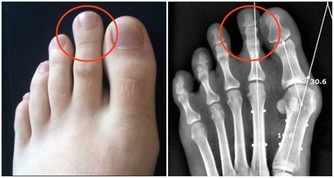

多汗的第一判斷1.夜間盜汗→ 結核病結核病典型的全身表現中包括午後低熱和夜間盜汗。

很多患者都反映無論春夏秋冬,晚上睡覺醒來後常常衣服被子全部都被汗水浸濕。

結核病在中國是一個比較令人頭疼的健康問題,所以你親愛的他如有上述症狀你就需要和醫生交流了。